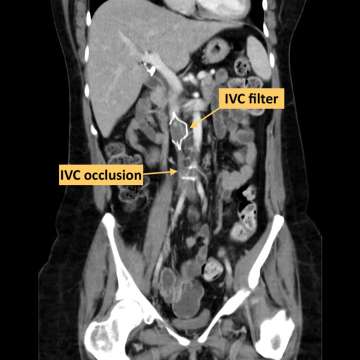

IVC Filter

IVC Occlusion

When clot around the IVC filter remains there for an extended period it can lead to a complete permanent blockage of the IVC, also known as IVC occlusion. This leads to long term leg swelling, pain and immobility. Removing the IVC filter and then opening up the IVC to allow normal blood flow can lead to relief of these symptoms. This can be achieved by our expert IR team using minimally invasive techniques that allow patients to rapidly improve their quality of life, all without large surgical procedures.